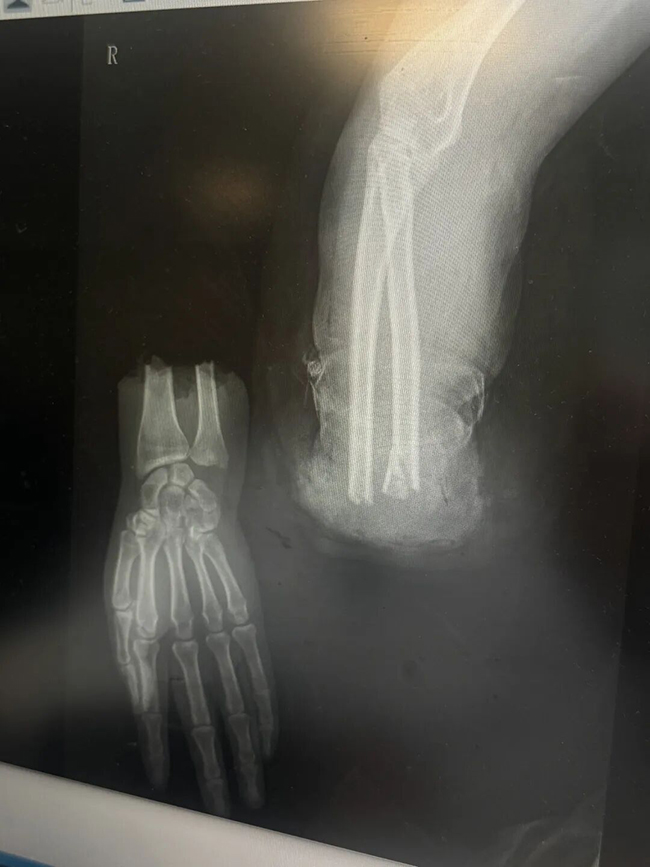

手术由手外科副主任医师邢树国主刀。他先为患者离断的肢体两端进行彻底清洗,然后将前臂的两根骨头——尺骨和桡骨——进行内固定。紧接着,他在显微镜下用比头发丝还细的缝线,精准地接通了尺动脉、桡动脉以及其伴行静脉。

从患者进入手术室到重新建立血供,整个过程不到两小时。当看到离断的手重新恢复红润,手术室里的每一个人都松了一口气。为确保离断肢体的再植成功和后期的功能恢复,之后又在背侧吻合了多根静脉,并修复了断端的肌肉和神经。